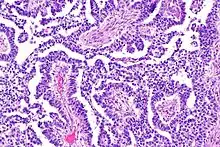

A micrograph view of dysgerminoma, showing actively dividing lobulated nuclei.[4]

Dysgerminomas are comparable to testicular seminomas and account for approximately 32- 37% of all OGCTs.[1] They are particularly prominent in individuals with dysgenic gonads of 46, XY pure gonadal dysgenesis patients.[1] Based on gross examinations, dysgerminomas are characterized by having a ‘solid, lobulated, tan, flesh-like gross appearance with a smooth surface'.[1] Microscopically, the cellular structure is distinguished by a round-ovoid shape containing ample eosinophilic cytoplasm and an irregularly shaped nuclei.[1] The uniformly positioned cells are separated through the fibrous strands and lymphocytic infiltration is commonly observed.[5]